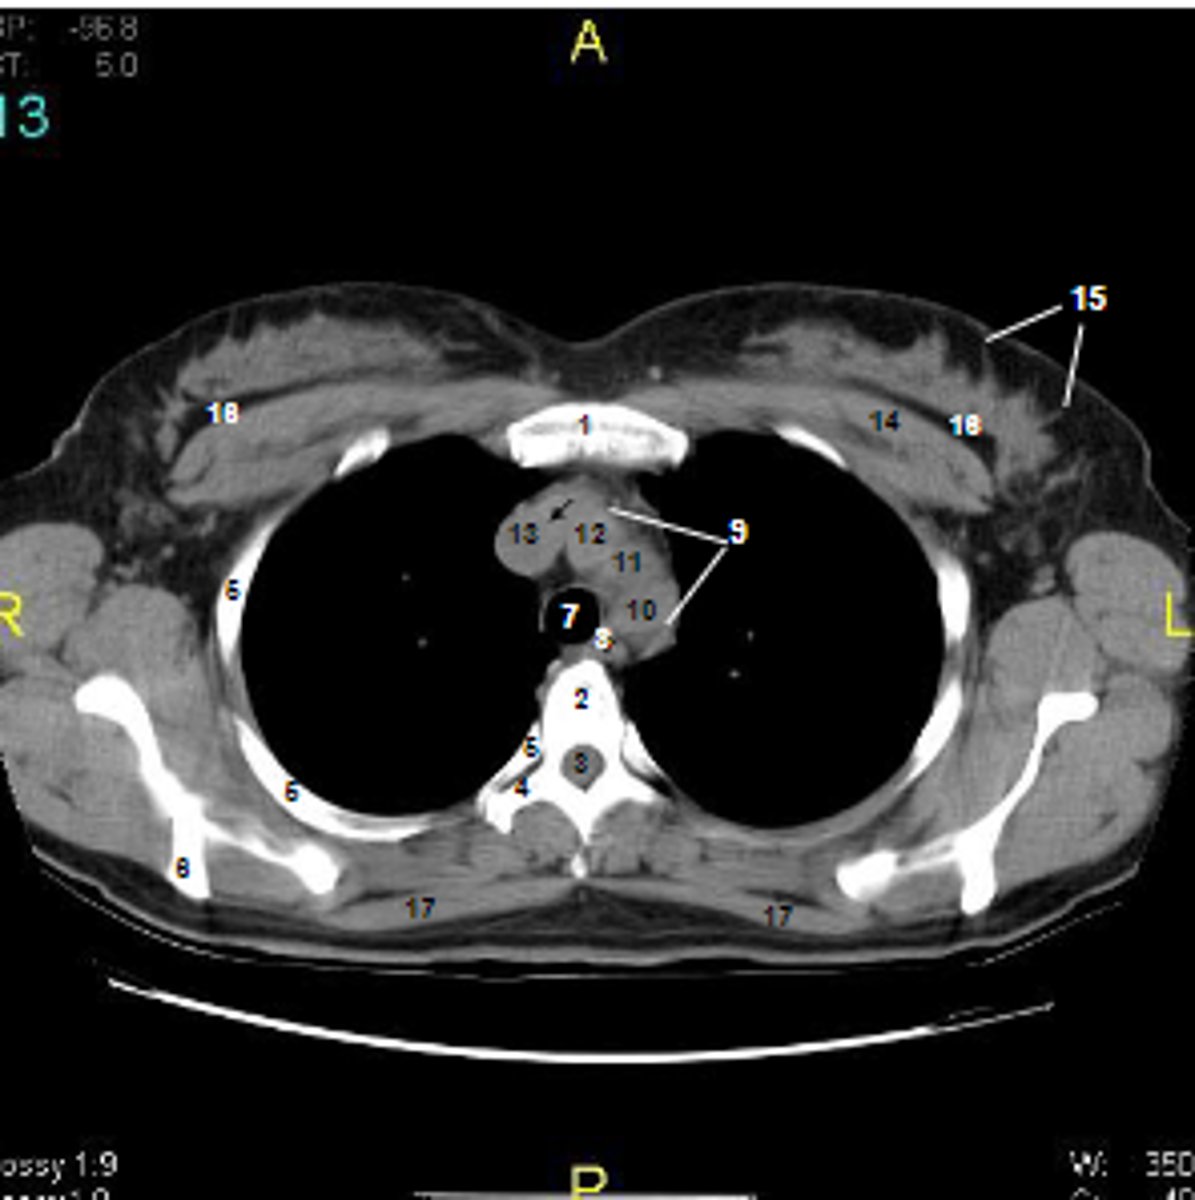

1

at what number is the sternum

2

at what number is the vertebral body

3

at what number is the vertebral canal/ spinal cord

4

at what number is the transverse process of vertebra

5

at what number is the rib

6

at what number is the spine of scapula

7

at what number is the trachea

8

at what number is the esophagus

9

at what number is the arch of aorta

10

at what number is the left subclavian artery

11

at what number is the common carotid artery

12

at what number is the brachiocephalic trunk

13

at what number is the superior vena cava

14

at what number is pectoralis major

15

at what number are Cooper's ligaments

16

at what number is the retromammary space

17

at what number is trapezius